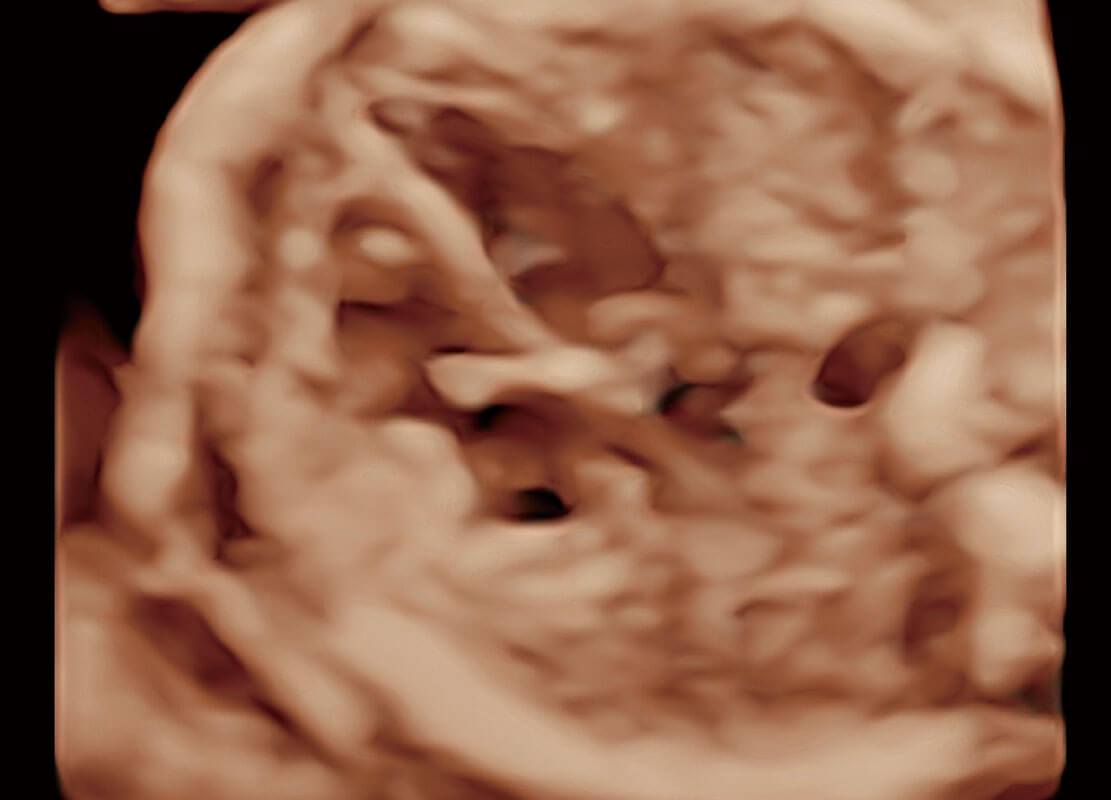

腔內(nèi)三維-光影成像

光影成像-孕囊